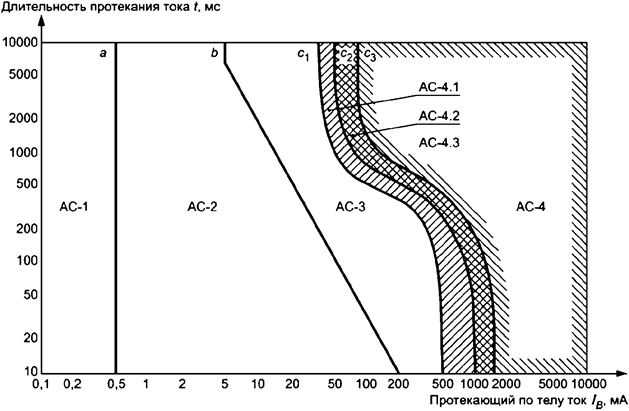

В результате приведения результатов экспериментов на животных к живым людям для пути протекания тока от кисти левой руки до ступней обеих ног была разработана условная эмпирическая кривая c1 (см. рисунок А.19). Если параметры на графике ниже этой кривой, то ФЖ маловероятна. Высокий уровень для малых длительностей воздействия от 10 до 100 мс был принят в виде снижающейся линии от 500 до 400 мА. На основе сведений по несчастным случаям с электричеством низкий уровень для длительностей воздействия более 1 с был принят в виде снижающейся линии от 50 мА при 1 с до 40 мА при длительностях воздействия более 3 с. Оба эти уровня соединены гладкими кривыми.

На основе статистического анализа результатов экспериментов с животными были разработаны кривые c2 и c3 (см. рисунок А.19), которые определяют вероятность фибрилляции примерно 5% и 50% соответственно. Кривые c1, c2 и c3 относятся к пути протекания тока от кисти левой руки до ступней обеих ног.

В таблице 11 даны границы времятоковых областей для различных физиологических реакций при протекании тока от кисти руки до ступней ног.

|

Область |

Границы |

Физиологические реакции |

|

АС-1 |

До 0,5 мА на кривой a |

Возможны какие-либо ощущения, но без реакции "испуг" |

|

АС-2 |

От 0,5 мА до кривой b |

Вероятны ощущения и непроизвольные сокращения мышц, но, как правило, без вредных физиологических воздействий |

|

АС-3 |

Кривая b и выше |

Сильные непроизвольные мышечные сокращения. Сложности с дыханием. Обратимые нарушения функции сердца. Может иметь место сковывание мышц. Влияние растет с увеличением силы тока. Как правило, не происходит внутренних повреждений |

|

АС-4 * |

Выше кривой c1 |

Могут иметь место патофизиологические воздействия, такие как остановка сердца, остановка дыхания, ожоги и другие повреждения клеток. Вероятность возникновения ФЖ растет с увеличением силы тока и его длительности |

|

c1 - c2 |

АС-4.1 - вероятность ФЖ увеличена до 5% | |

|

c2 - c3 |

АС-4.2 - вероятность ФЖ составляет до 50% | |

|

За кривой c3 |

АС-4.3 - вероятность ФЖ выше 50% | |

|

* При длительности протекания тока менее 200 мс ФЖ наступает только при воздействии в пределах периода уязвимости, если превышены соответствующие пороги. Рисунок А.19 в части ФЖ относится к пути протекания тока от кисти левой руки до ступней ног. Для других путей протекания тока необходимо применять коэффициент сердечного тока. | ||

Рисунок А.19 - Общепринятые времятоковые области, определяющие воздействия переменного тока (частотой от 15 до 100 Гц) на человека для пути протекания тока от кисти левой руки до ступней обеих ног (см. таблицу 11)